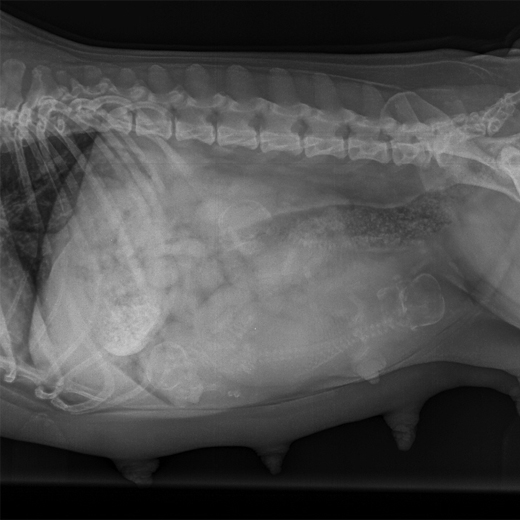

Wir sind sehr traurig, heute ist Boulot nach kurzer Krankheit verstorben.